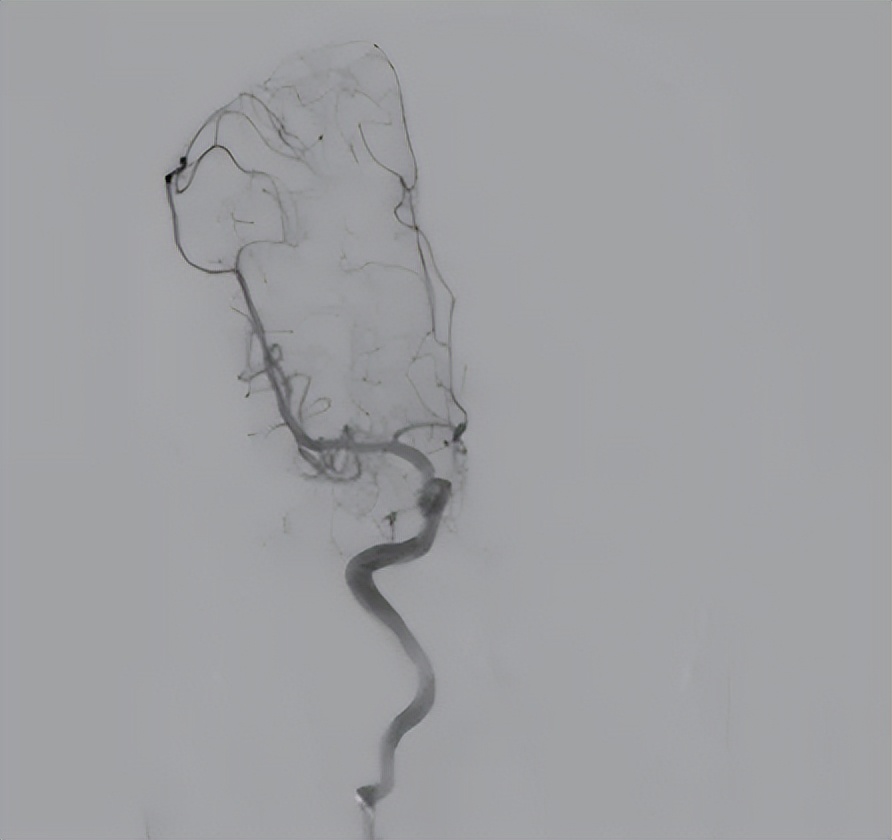

预后:术后患者神志清楚,颅内情况稳定,术前肢体瘫痪症状明显改善,下肢肌力恢复至2~3级,上肢肌力1~2级。术后1个月复查脑血管造影,显示右侧畸形团已切除,未见残留显影。患者后续仍需定期随访与康复训练。

图10 患者术后复查血管造影